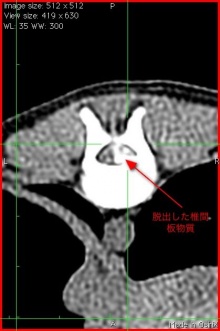

CTの検査をおこなってみるとT(胸椎)の11番と12番の間と12番と13番の間に椎間板ヘルニアが観察され、とくに12番と13番の間ではかなりひどい椎間板物質の脱出が見られました。写真で白く写っているのが飛び出した椎間板物質です。手術はうまくいきましたので、歩けるようになってくれると思います。